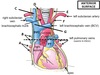

Name structures A to F

A - Inferior vena cava

B - Superior vena cava

C - Aorta

D - Pulmonary trunk

E - Left pulmonary artery

F - Left pulmonary veins